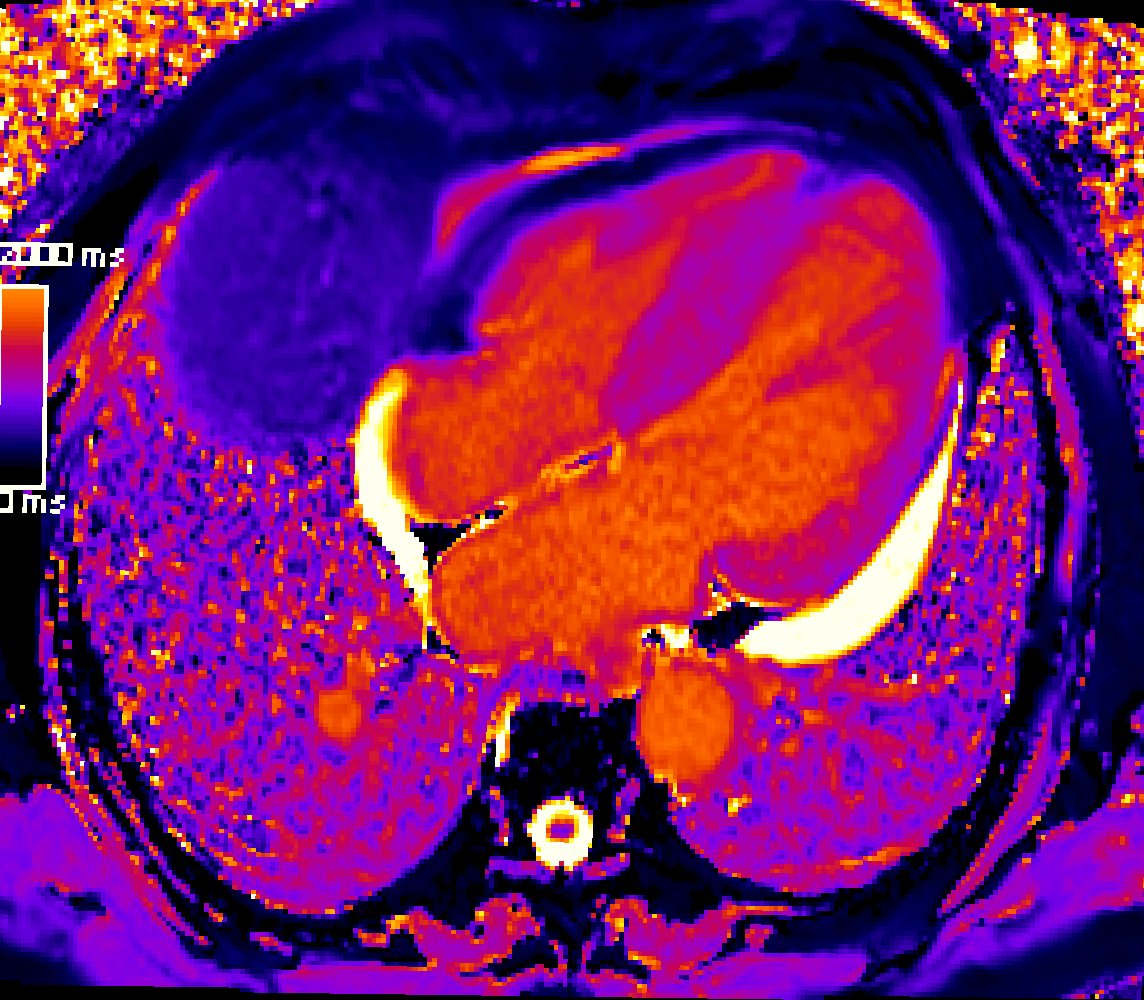

Just published on @ESCHeartFailure our meta-analysis on the prognostic role of T1 mapping in NIDCM. Both T1 mapping and ECV were associated with increased risk of the primary endpoint of MACE and the secondary endpoint of heart failure and arrhythmic-related events.